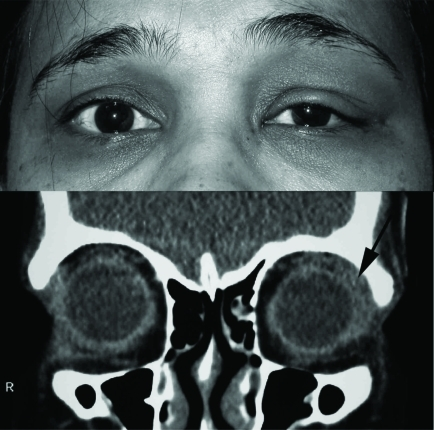

- 급성: 상외측 안검 부종, 통증, 발적, S-shaped lid

- S자형 안검 (S-shaped lid): 상안검 외측 부종으로 S자 모양

- CT/MRI: 눈물샘 비대

- S-shaped lid: 눈물샘 비대의 특징적 소견 ⭐⭐